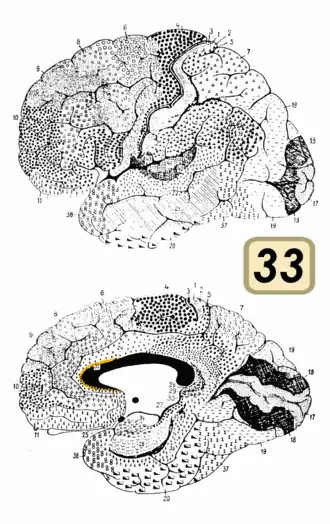

Brodmann area 33

Brodmann area 33 (shown in orange) | |

Brodmann area 33, also known as pregenual area 33, is a subdivision of the cytoarchitecturally defined cingulate region of cerebral cortex. It is a narrow band located in the anterior cingulate gyrus adjacent to the supracallosal gyrus in the depth of the callosal sulcus, near the genu of the corpus callosum.[1] Cytoarchitecturally it is bounded by the ventral anterior cingulate area 24 and the supracallosal gyrus (Brodmann-1909). The pregenual area 33 is heavily involved in emotions, especially happy emotions.[2][3]